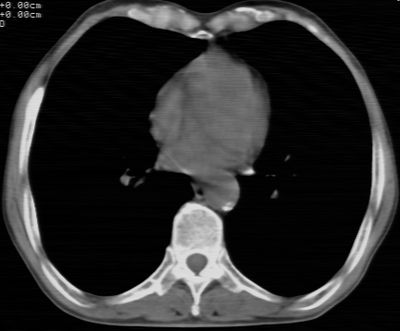

标题: CT24783:m71,既往肺心病史3年,现咳嗽,憋喘。 [打印本页]

标题: CT24783:m71,既往肺心病史3年,现咳嗽,憋喘。

1、左肺上叶spn,毛刺+分叶+血管集束征,考虑周围型肺癌可能性大

2、全小叶性肺气肿。

1)左肺上叶周围型肺癌可能。2)两肺全小叶型肺气肿。

左上周围型肺癌,全小叶型肺气肿。